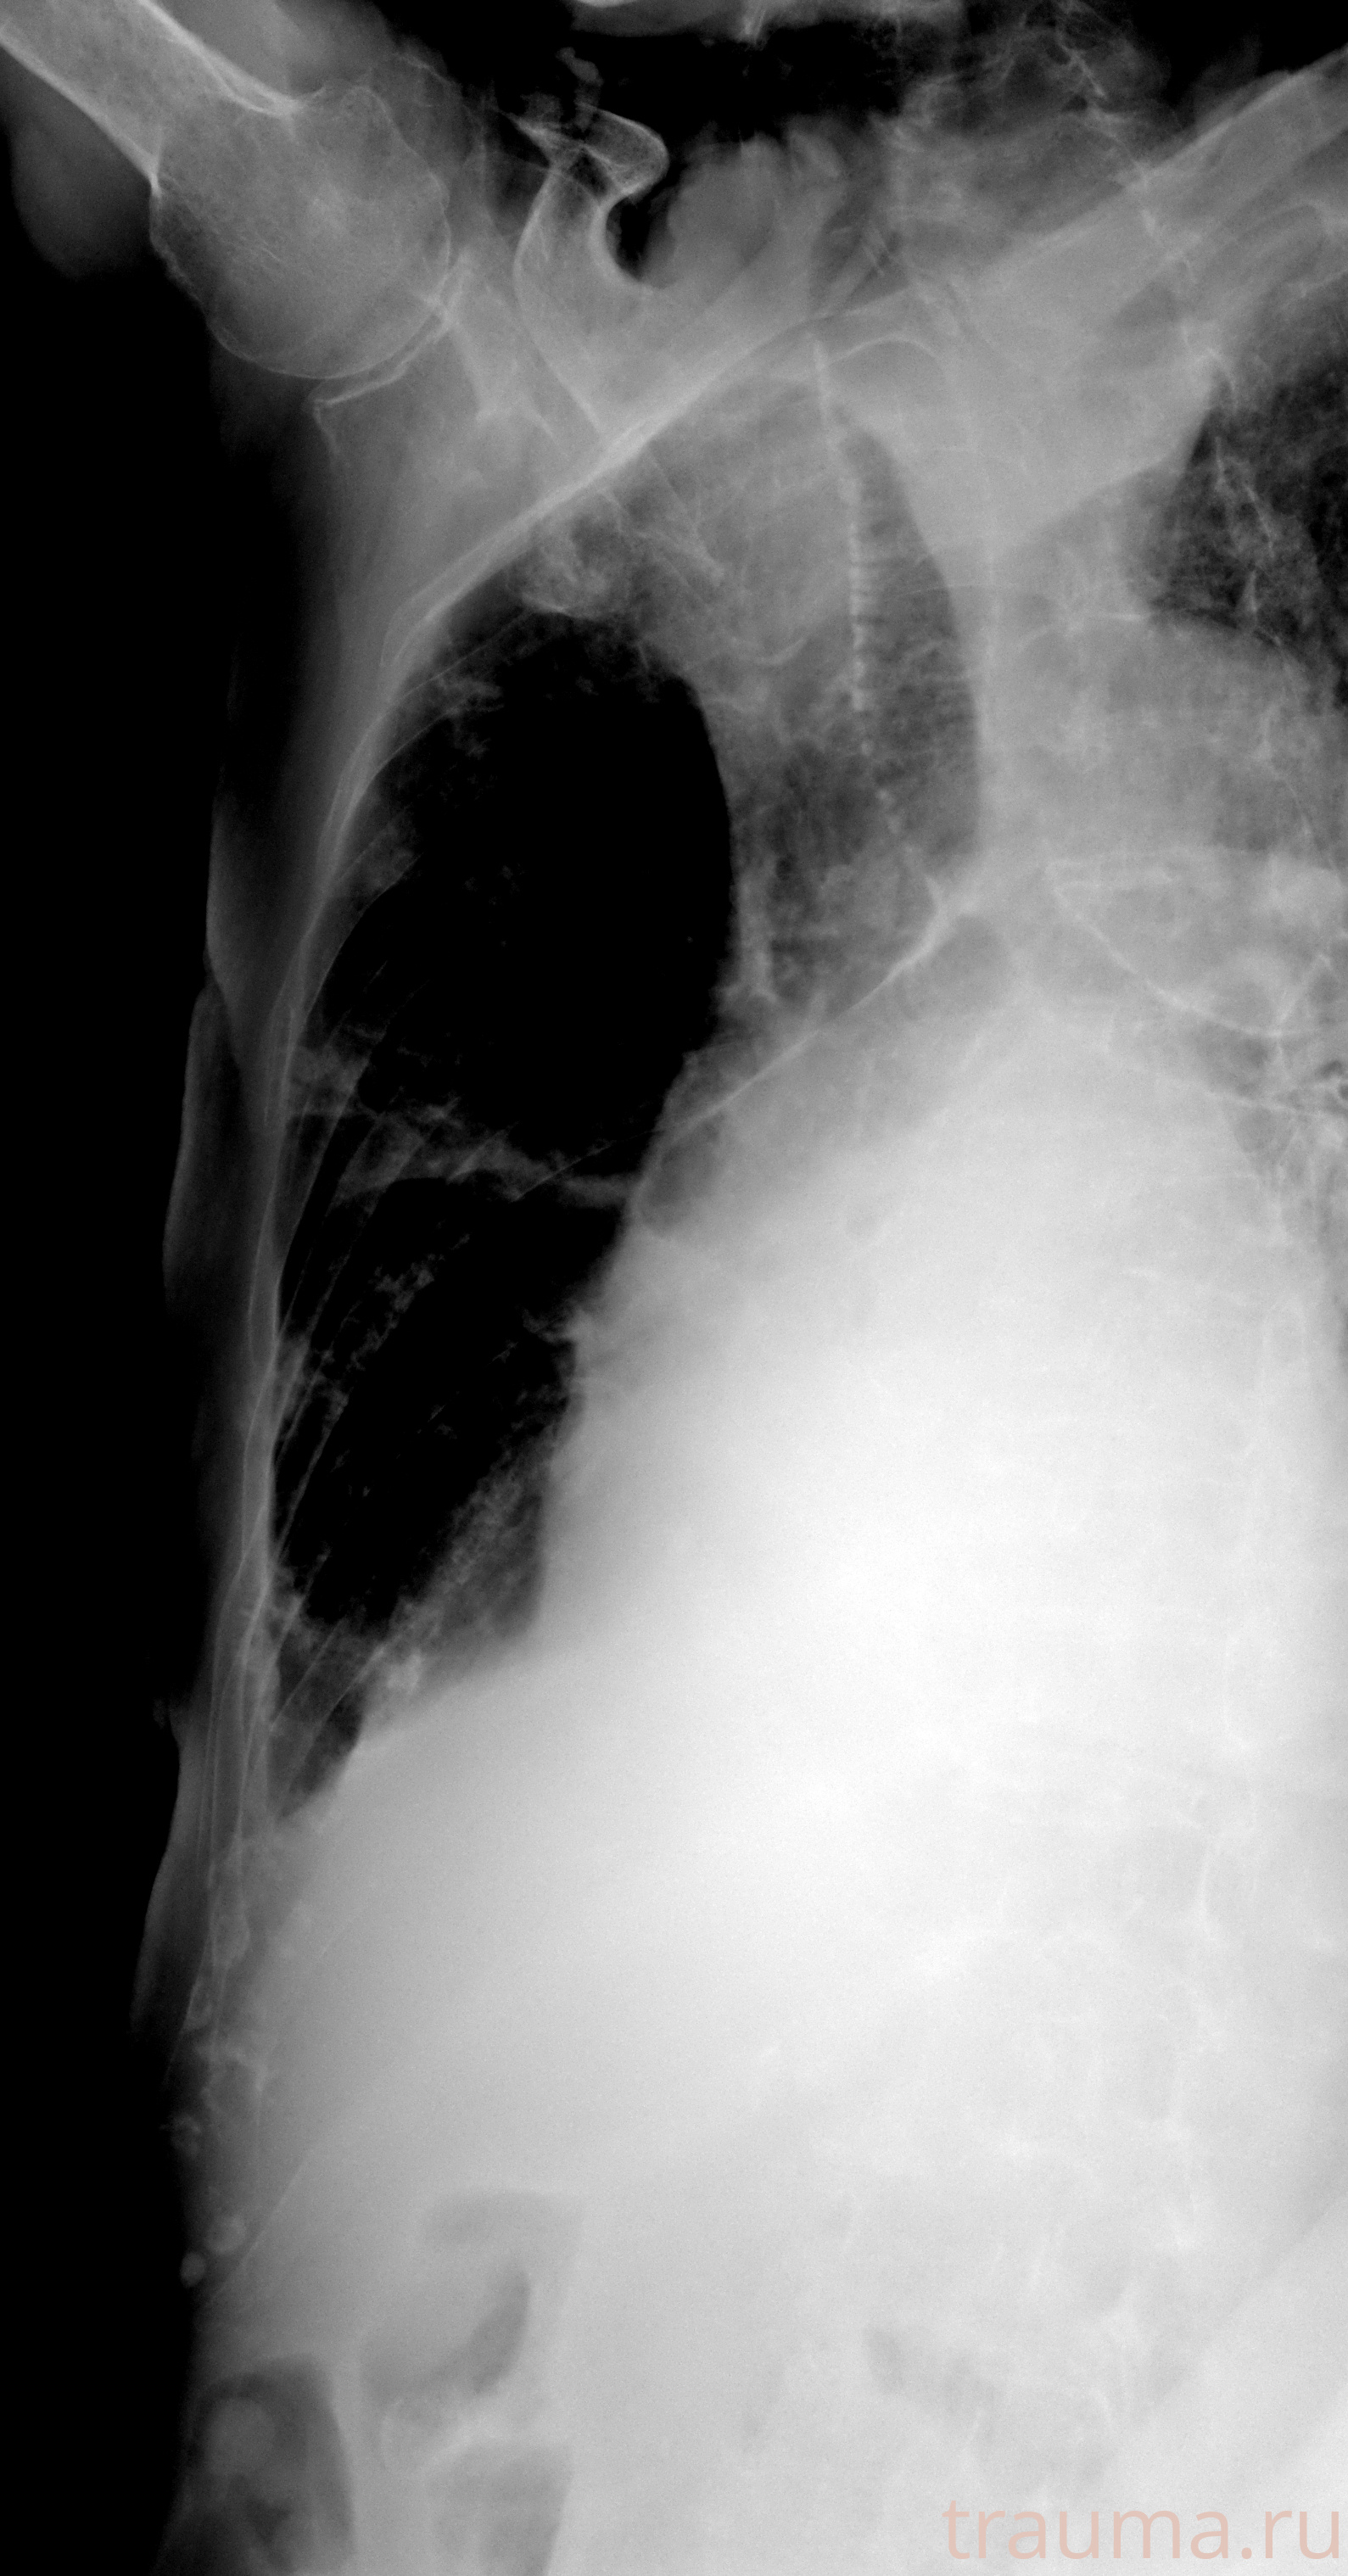

Рентгенограммы

Рентген на дому: по вашему адресу приезжает врач-рентгенолог, травматолог-ортопед с мобильным рентгеновским аппаратом, проводит диагностику травмы или заболевания, делает необходимые рентгенограммы, дает рекомендации по дальнейшему лечению. Получить качественные снимки в домашних условиях возможно благодаря уникальной методике, разработанной МосРентген Центром для института  Склифосовского

при переломе шейки бедра и пневмонии от компании МосРентген Центр - партнера Института имени Склифосовского